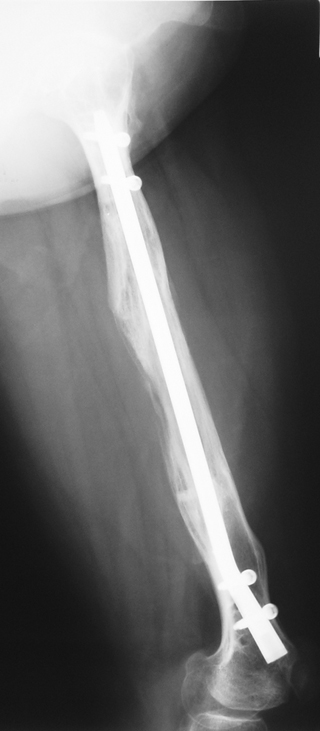

3. POSTTRAUMATIC LOWER LIMB SHORTNESS (MALUNION)

This type of shortness occurs after a fracture heals in a shortened position. Most cases are seen in adults and can be treated with one lengthening operation. Additional deformities can be corrected simultaneously. Most of these cases can be treated with lengthening over nail or just corrections and intramedullary nailing.